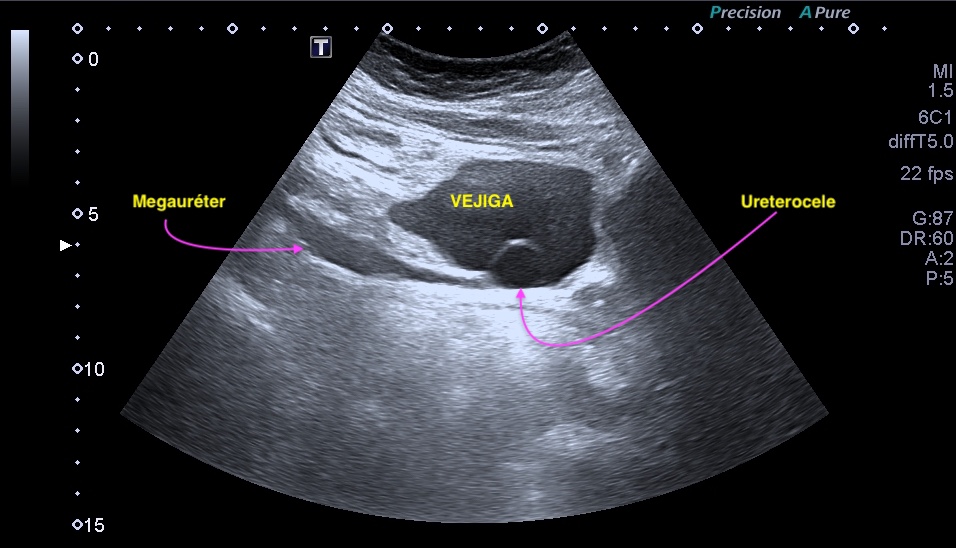

¡Hola a todos! A petición de los votantes del perfil de Instagram quiero hablar sobre un tema de gran importancia en el campo de la urología: el urotelioma vesical y su relación con la hematuria. Además, destacaré la relevancia de realizar un estudio de ecografía reno vesical para detectar esta afección y describiré los hallazgos ecográficos típicos, con un enfoque especial en la importancia de la vascularización mediante registro Doppler.

El urotelioma vesical es un tipo de cáncer que se origina en el revestimiento interno de la vejiga, conocido como urotelio. Una de las señales de alarma más comunes de esta enfermedad es la hematuria, es decir, la presencia de sangre en la orina. La hematuria puede manifestarse de diferentes formas, desde ligeras trazas de sangre (perceptibles solo en analítica o micro-hematuria) hasta una coloración rojiza intensa en la orina. Es importante destacar que la presencia de sangre en la orina no siempre indica la presencia de un urotelioma.

La ecografía reno vesical es un estudio no invasivo permite examinar la vejiga y los riñones, proporcionando información valiosa sobre posibles anomalías o lesiones presentes. En el caso del urotelioma, la ecografía puede revelar la presencia de masas o tumores en la vejiga, así como características específicas que indican la posible malignidad de la lesión.

Al realizar una ecografía reno vesical, los hallazgos ecográficos típicos del urotelioma incluyen la visualización de una masa sólida en la vejiga.

Esta masa puede presentar una apariencia heterogénea, con áreas hipoecoicas (menos ecogénicas) y áreas hiperecoicas (más ecogénicas) en relación con el tejido circundante. Además, puede observarse un crecimiento intraluminal, lo que significa que la masa se proyecta hacia el interior de la vejiga.